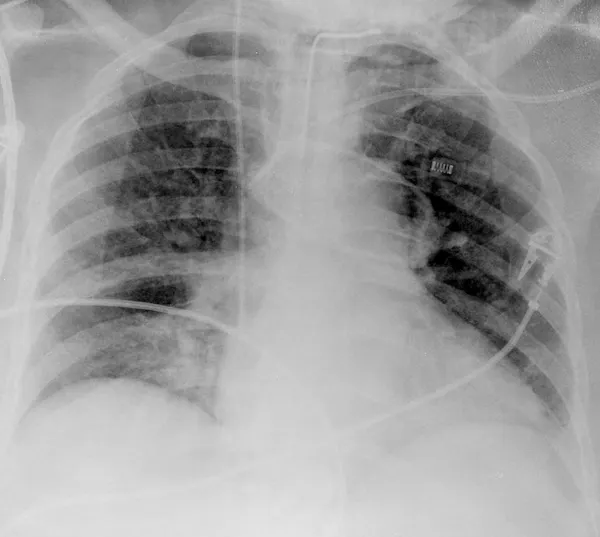

Se recurre a esta técnica de imagen porque, debido a la afectación primaria del sistema respiratorio, la infección por SARS-CoV-2 deja evidencias radiológicas de neumonía visibles bajo los rayos X. Concretamente, la neumonía asociada a la covid-19 produce sombras en los pulmones conocidas como opacidad de vidrio esmerilado. Estas opacidades suelen aparecer con una distribución periférica o posterior, principalmente en los lóbulos inferiores y con menos frecuencia en el lóbulo medio derecho.

En los dos primeros días de la infección, el 50% de los pacientes de covid-19 ya muestra lesiones pulmonares parenquimatosas, superando el 90% entre los 3 y 5 días. Lo sorprendente es que esto ocurre incluso en pacientes asintomáticos. Por ello, complementar la RT-PCR con una radiografía de tórax mejora la sensibilidad en el diagnóstico, reduciendo significativamente el número de falsos negativos. Es importante porque los falsos negativos son precisamente el talón de Aquiles de la prueba RT-PCR, cuya sensibilidad oscila entre el 70-90%. Otra ventaja importante es que la radiografía está lista en cuestión de minutos.